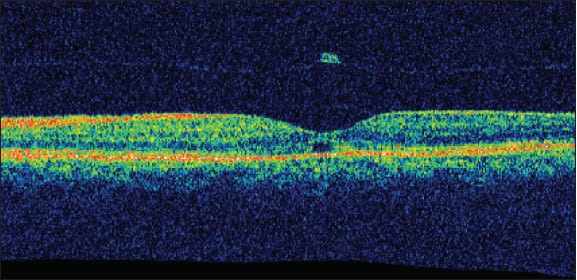

Three months later, there was no change in metamorphopsia in the left eye and visual acuity was stable at 20/200, but upon examination, it seemed that the hole was closed. Stratus OCT demonstrated complete PVD with closure of the macular hole in the left eye. Foveal contour returned to an almost normal configuration, and a small subretinal cyst, photoreceptor discontinuity, and an operculum attached to the detached vitreous are all that remained of the once full-thickness macular hole (Figure 3). Over five months of follow-up, visual acuity of the left eye improved to 20/50, and Spectralis HR-OCT demonstrated almost complete absorption of the cyst and restoration of the normal foveal contour. Only a subtle discontinuity of the photoreceptor layer was still noticeable — a fact that may explain the still decreased visual acuity (Figure 4). The right eye remained unchanged during this period.

Figure 4. Spectralis HR-OCT of the left eye after five months, demonstrating almost complete absorption of the cyst, restoration of a normal foveal contour, an operculum, and a remaining subtle discontinuity of the photoreceptor layer.